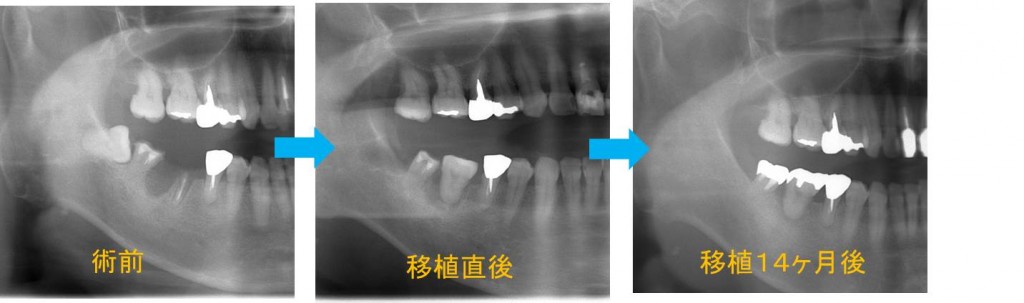

移植した親知らずのレントゲン像を見ていきます。

左写真から術前→移植直後→移植14か月後です。